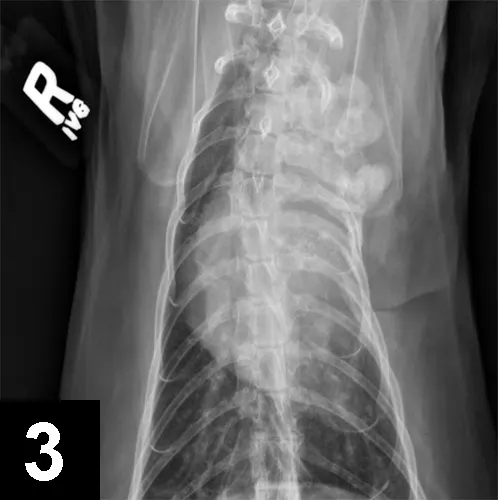

FIGURE 1

Patient showing classic signs of right-sided Horner syndrome: miosis, ptosis, enophthalmos, and elevated nictitans.

Horner syndrome (Figures 1–3) is not a disease but a myriad of clinical signs caused by sympathetic denervation to the eye. Disease affecting any portion of the sympathetic pathway can lead to ipsilateral neurologic dysfunction.